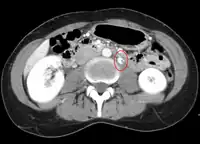

The nutcracker syndrome results from compression of the left renal vein between the aorta and the superior mesenteric artery.

The nutcracker syndrome (NCS) results most commonly from the compression of the left renal vein (LRV) between the abdominal aorta (AA) and superior mesenteric artery (SMA), although other variants exist.[1][2] The name derives from the fact that, in the sagittal plane and/or transverse plane, the SMA and AA (with some imagination) appear to be a nutcracker crushing a nut (the renal vein).